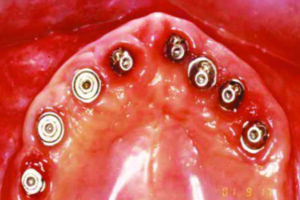

PRASA: il primo rivoluzionario sistema biomeccanico totalmente italiano rispettoso della gengiva e dei carichi masticatori.

Dalla genialità italiana l’ innovazione della connessione biologicamente compatibile : sappiamo da molti anni che il titanio medicale è un metallo che inserito nell’osso umano non causa reazioni avverse. L’unica difficoltà, per l’implantologia moderna, era rappresentata dalle infiltrazioni di batteri presenti nel cavo orale, nel confine tra radice artificiale ed elemento dentario.

Poteva succedere che questi batteri dessero luogo a gengivite e perimplantite (infiammazione intorno all’impianto) con perdita di attacco dei tessuti e conseguente danneggiamento della riabilitazione implantoprotesica.

La tecnica PRASA permette la creazione di un rispettoso confine tra strutture sotto e sopra gengivali ricreando il cosiddetto spazio fisiologico gengivale, permettendo la creazione di una “guarnizione gengivale” naturale che impedisce le proliferazioni batteriche tanto temute.

Risultato: durata dell’impianto, gengive sane ed assenza di “cattivo” odore.